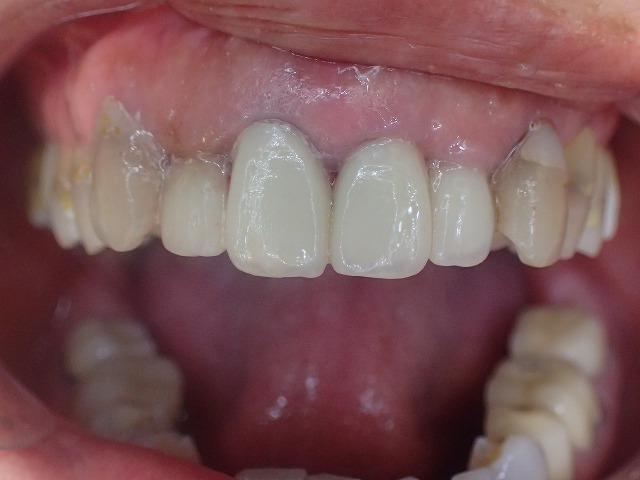

顔面に対して水平垂直も位置決めをして

左右対称に形態修正後、磨きをかけました。

よいものは長持ちです。

20年以上前の補綴物ですが綺麗になりました。